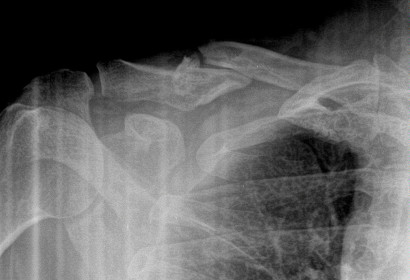

Distal Clavicle Fracture Repair with Bone Tunnels and Suture

Fracture on the left with the repair on the right.